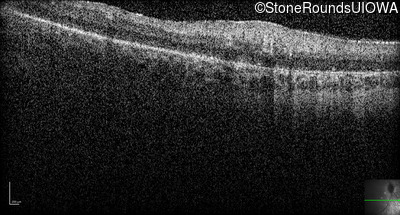

Optical Coherence Tomography - Right -

No Light Perception

Exemplar

Optical Coherence Tomography - Left -

Light Perception